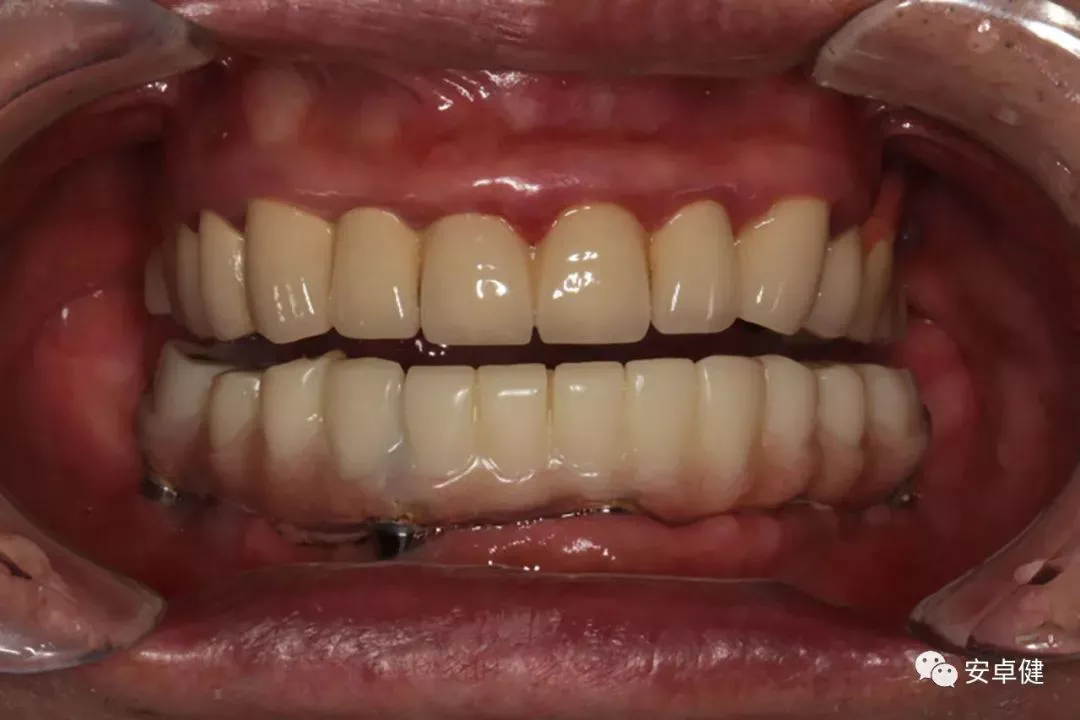

最终修复后8个月

戴牙后8个月复诊正面咬合照

戴牙后8个月复诊正面微张照

戴牙后8个月复诊合面照

戴牙后8个月复诊上颌正面照

戴牙后8个月复诊下颌正面照

戴牙后8个月复诊侧方咬合照

咬合检查

• 随访可见患者口腔卫生状况可,牙龈无红肿;

• 下颌修复体状态良好,无修复体机械并发症;

• 种植体基台稳定性良好,无松动;

• 种植体无松动,周围无红肿、溢脓及疼痛表现;

• 正中、前伸及侧方咬合检查可见咬合印记分布均匀,咬合关系良好;

• 患者反映日常使用良好,舒适性佳,满意度高。